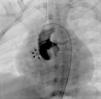

Case 2A 3-year-old asymptomatic boy was referred due to a murmur suggestive of a ventricular septal defect. In the echocardiogram, a turbulent flow was evident in the proximal ascending aorta, as well as in the right ventricular wall. In order to clarify the morphology of this apparent fistulous tract, he underwent a cardiac computerized tomography scan, which confirmed the presence of a fistula between the ascending aorta and the RV (Figure 2).